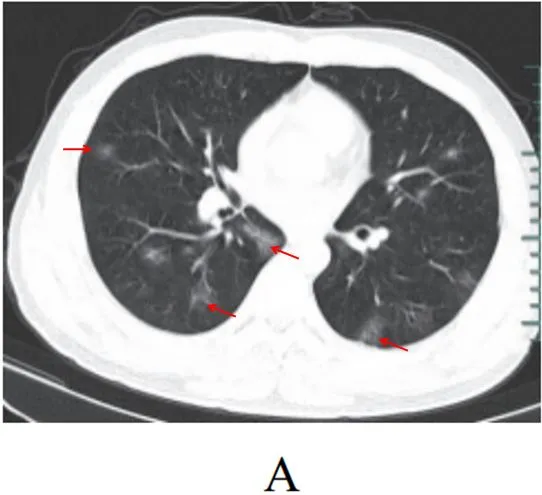

病灶以肺外围背侧为主,以两肺下叶为著,与胸膜常紧贴,提示新冠肺炎病变多首先侵犯皮层肺组织的细支气管及肺泡上皮,病灶分布逐步从外周向中央扩展(图 2-1)

图2-1 早期病灶多数分布贴近胸膜(共4张)